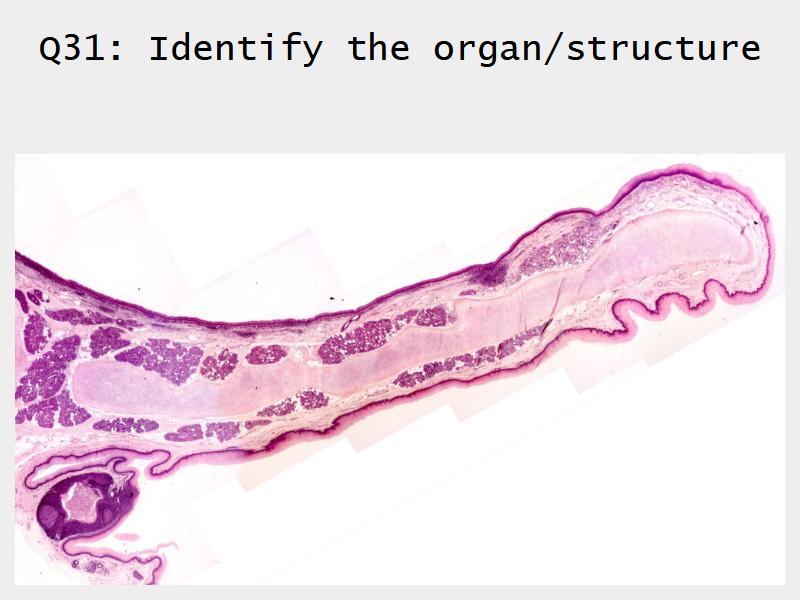

- Slide 111: Epiglottis

Epiglottis